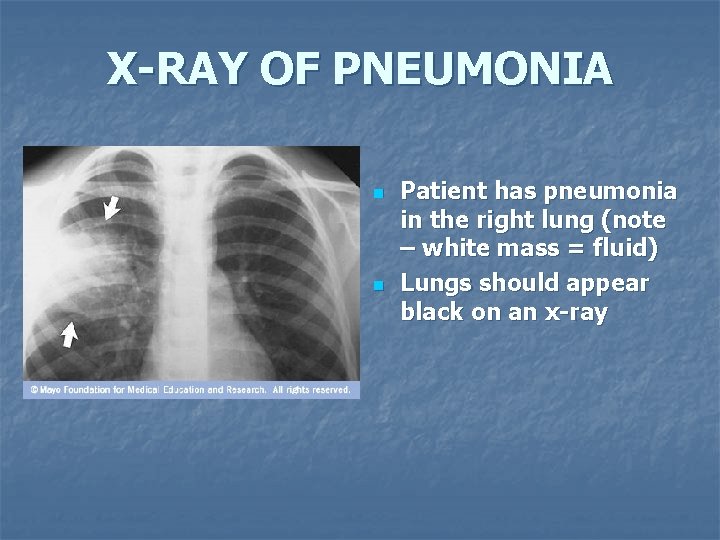

X-RAY OF PNEUMONIA n n Patient has pneumonia in the right lung (note – white mass = fluid) Lungs should appear black on an x-ray